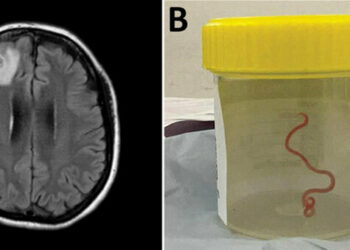

L'esperto di malattie infettive coinvolto nel caso australiano del verme rinvenuto vivo nel cervello umano aveva previamente avvisato che il...